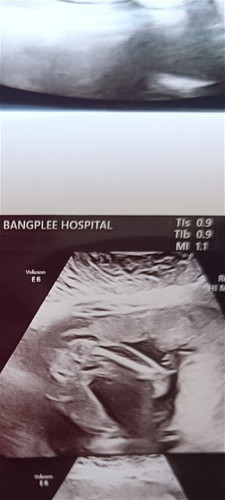

สอบถามแม่ๆค่ะแบบนี้ผู้หญิงหรือผู้ชายค่ะ หมอบอกน่าจะผู้หญิง

หนีบ ๆ ขา ไม่ชัวร์เท่าไหร่ค่ะ รอลุ้นเดือนหน้านะแม่